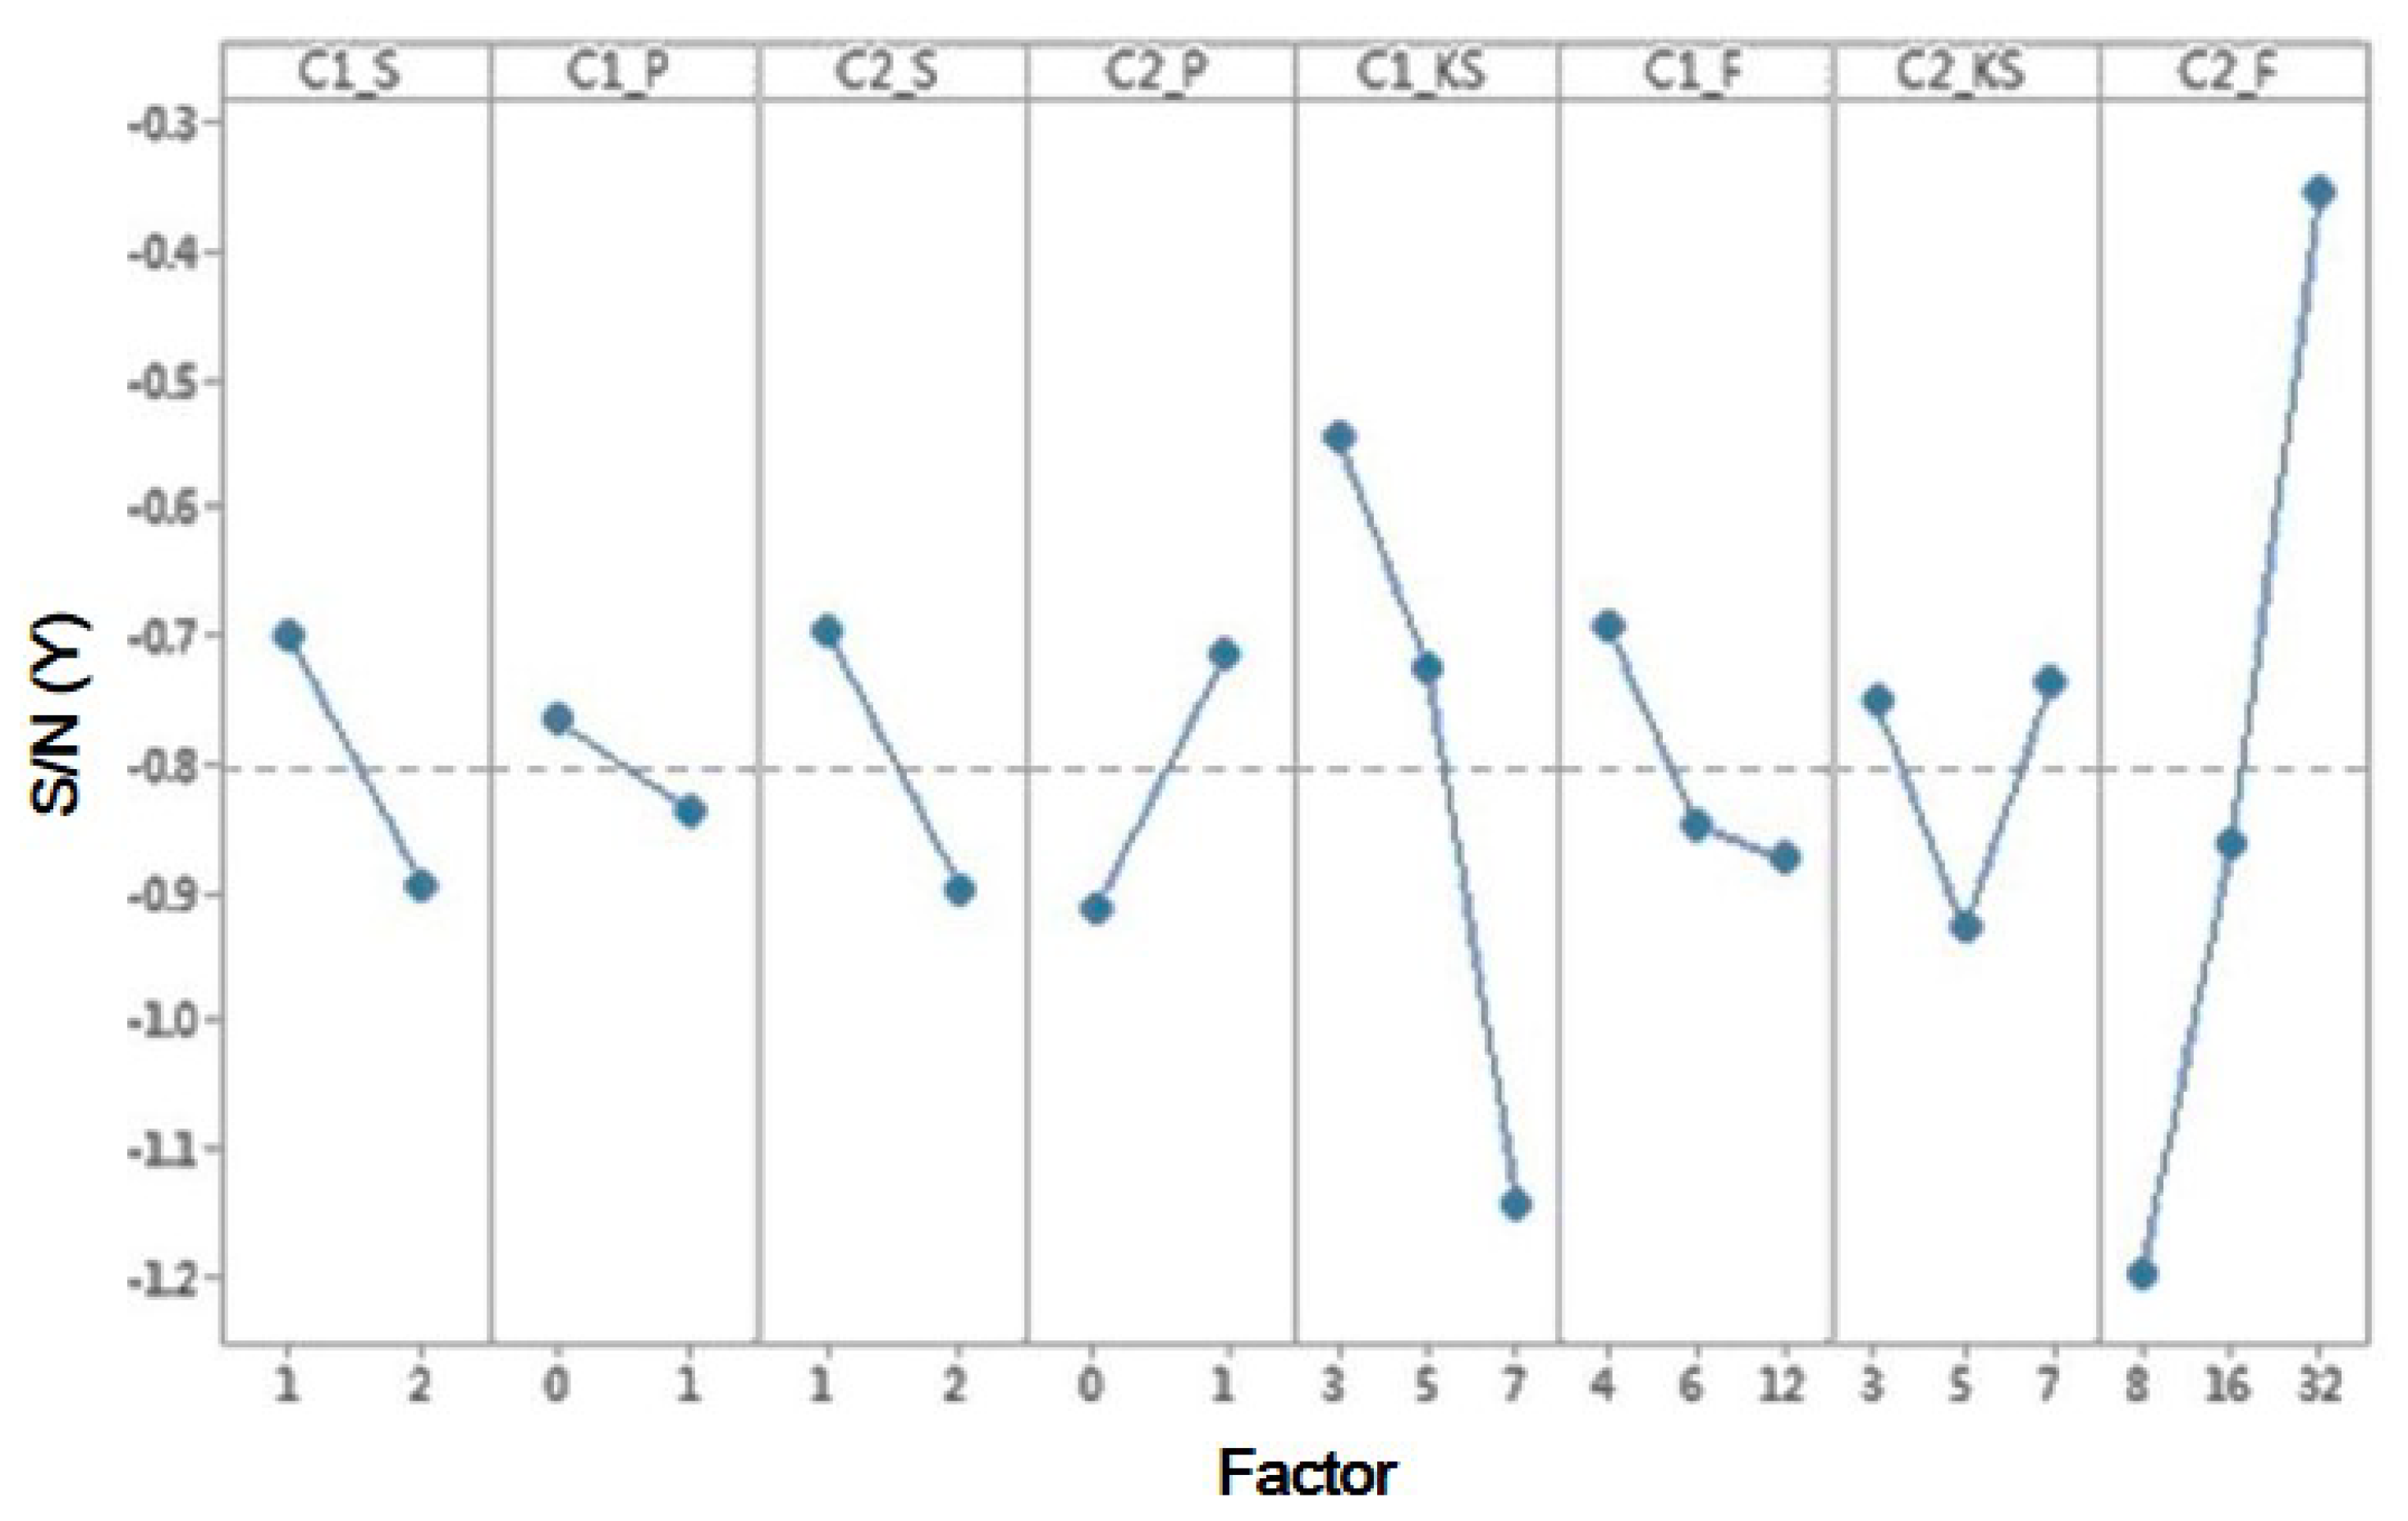

3.2. SPIE-AAPM

| Level | Factors | |||||||

|---|---|---|---|---|---|---|---|---|

| A C1_S | B C1_P | C C2_S | D C2_P | E C1_KS | F C1_F | G C2_KS | H C2_F | |

| 1 | −0.1761 | −0.45716 | −0.33985 | −0.69967 | −0.16709 | −0.30776 | −0.47113 | −0.83316 |

| 2 | −0.68205 | −0.44783 | −0.5456 | −0.24574 | −0.41333 | −0.60539 | −0.38385 | −0.44508 |

| 3 | −0.77581 | −0.44307 | −0.50125 | −0.07798 | ||||

| Delta | 0.50595 | 0.00933 | 0.20575 | 0.45393 | 0.60872 | 0.29763 | 0.1174 | 0.75518 |

| Rank | 3 | 8 | 6 | 4 | 2 | 5 | 7 | 1 |

| Best level | 1 | 2 | 1 | 2 | 1 | 1 | 2 | 3 |

| Optimal parameter | 1 | 1 | 1 | 1 | 3 | 4 | 5 | 32 |